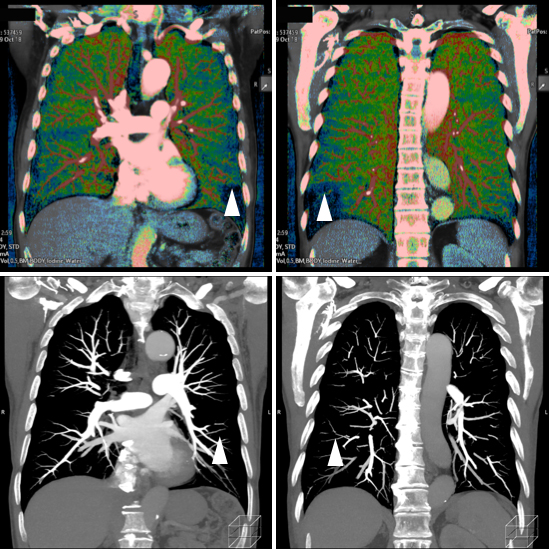

Dual energy CT

さらに、これら2台のCT装置にはdual energy システムも搭載しており、体内の物質を弁別する能力があります。特に造影剤の分布を定量的に評価可能なため、各臓器における造影剤の取り込み状況に加えて繊維化の度合いや出血との鑑別等への有用性が期待されます。また、様々なX線エネルギーをシミュレーションした画像も作成できるため、造影剤によるコントラストの向上による造影剤量の低減も可能です。